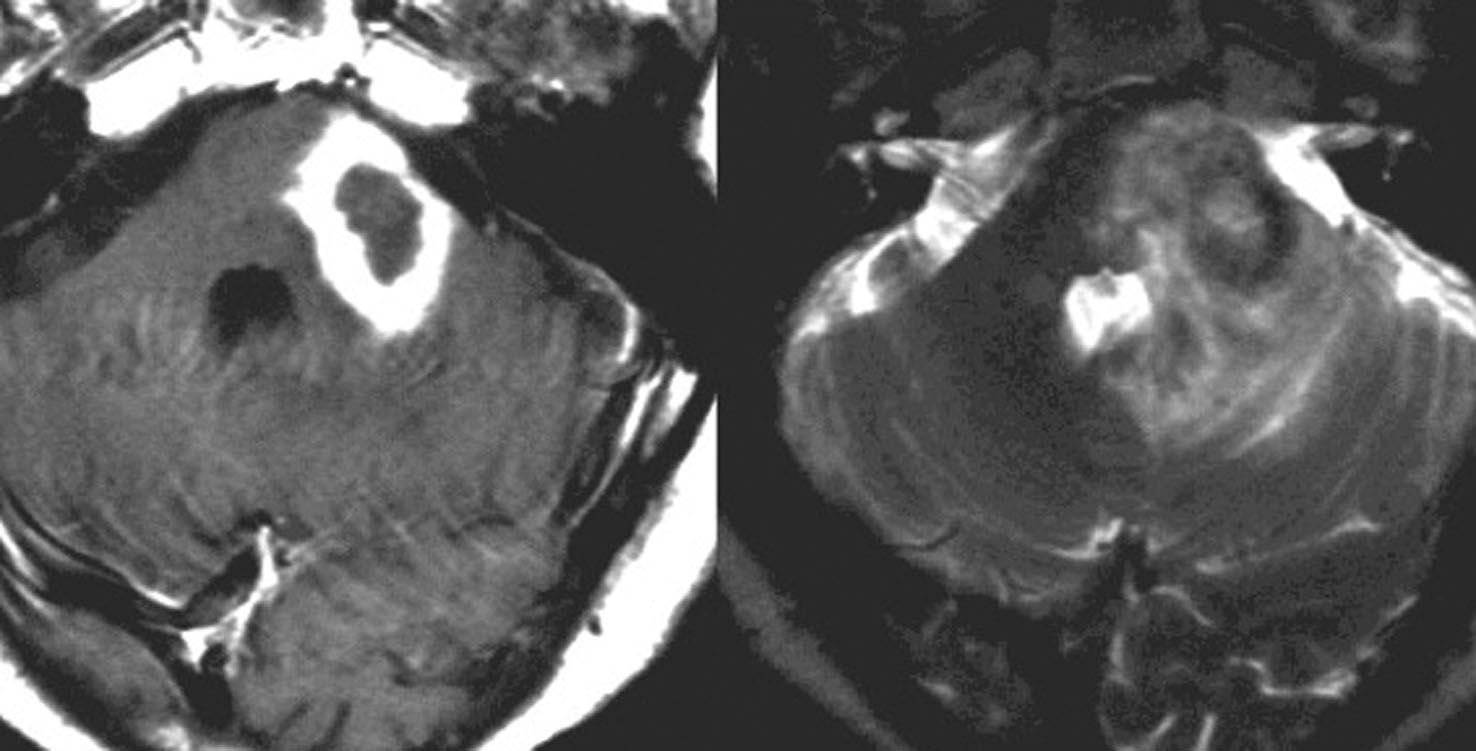

これは1990年代の古い例ですがリンパ腫の増大が早いことをお見せします。左側のはTHP-COPという化学療法をする前のものです。真ん中のは化学療法から4日目で,腫瘍は小さくなりました。でも,2コース目の化学療法の直前(4週間後)にもう一度MRIをしてみたらすごく大きくなっていました。この化学療法は効いているのだか効いていないのだか判らないことになります。化学療法を行なうならとても強い薬剤を使わなければなりませんし急がなければなりません。